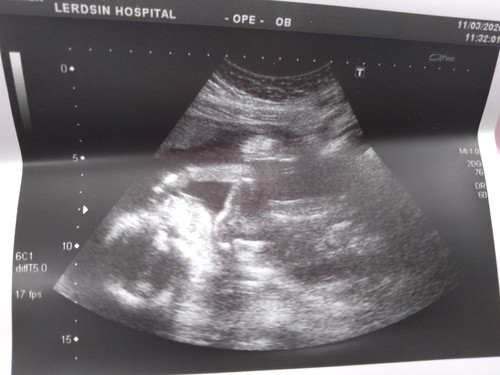

ตอนนี้21weekแล้ว ดิ้นเก่งมากโก่งตัวจนแม่นี้เจ็บท้องเลย5555 บ้านนี้กำหนดคลอด 22 กรกฏาคม อยากรู้ของแม่ๆบ้านอื่นกันบ้างได้ ญหรือช กันค่ะมาเล่าสู่กันฟังหน่อย??